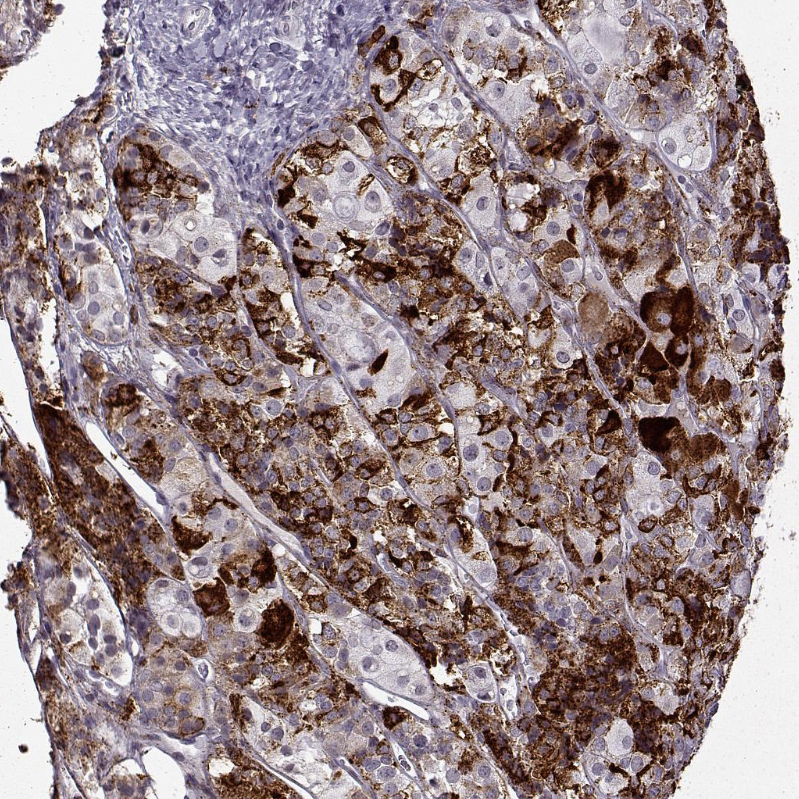

Immunohistochemistry analysis in human cerebral cortex and prostate tissues using HPA055177 antibody. Corresponding VGF RNA-seq data are presented for the same tissues.